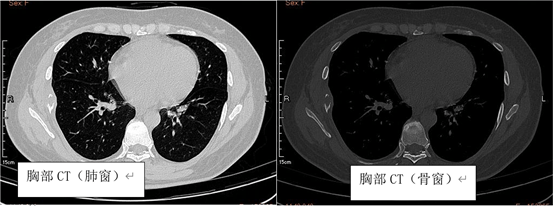

患者女性,52岁,因“右侧胸壁疼痛2周”就诊。患者2025年8月中旬开始无明显诱因下出现右侧胸壁疼痛,表现为右侧胸壁持续性钝痛,需口服NSAID类止痛药才能缓解,病程中,患者否认胸闷、气急、刺激性咳嗽、咳痰、咯血、发热等不适,患者遂于外院就诊,2025.08.28外院予以行胸部平扫CT检查提示右侧第7肋骨肿物伴骨质破坏,2025.08.30予以进一步行PET/CT检查提示右侧第7肋骨肿物,大小约2.0*3.0cm,伴周围骨质破坏,FDG代谢增高,SUVmax=8.6,考虑恶性病变可能,倾向原发,未见其他部位肿瘤性病变。后患者于我院就诊,入院予以肋骨三维CT重建(2025.09.02)提示右侧第7肋骨肿物伴病理性骨折,骨扫描(2025.09.03)提示右侧第7侧肋可见局部骨质密度减低伴骨质破坏,考虑恶性病变,余未见其他骨病变,头颅增强MRI检查未见颅内病变。

朗格汉斯细胞组织细胞增生症的影像学诊断首选PET/CT,尤其是对于骨骼病变的检出要优于CT和MRI,表现为高摄取的溶骨性改变。中枢神经系统病变首选MRI检查,肺部病变首选胸部CT。但LCH的确诊主要靠病理诊断,其主要病理形态学特点为:瘤细胞呈片、巢状分布,胞质丰富、淡染,细胞核呈肾形、咖啡豆样、有核沟,背景常伴有淋巴细胞、嗜酸性粒细胞、组织细胞、纤维母细胞及多核巨细胞。免疫组化特点为CD1a、Langerin(CD207)及S-100蛋白阳性,其中CD1a和Langerin的灵敏度及特异度均较高,是确诊LCH所必需的[3]。此外,超过50%的患者合并有BRAF-V600E的突变[4]。